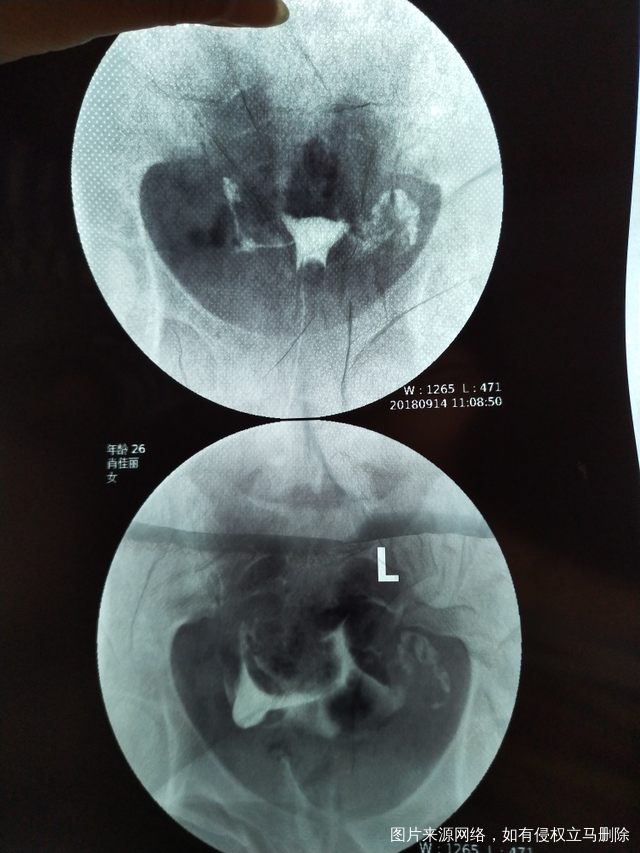

今天做了造影 医生帮我看下怎么样吧?